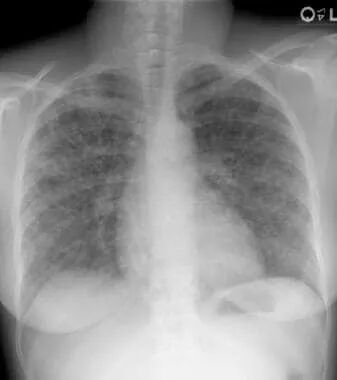

图1 双肺门淋巴结肿大